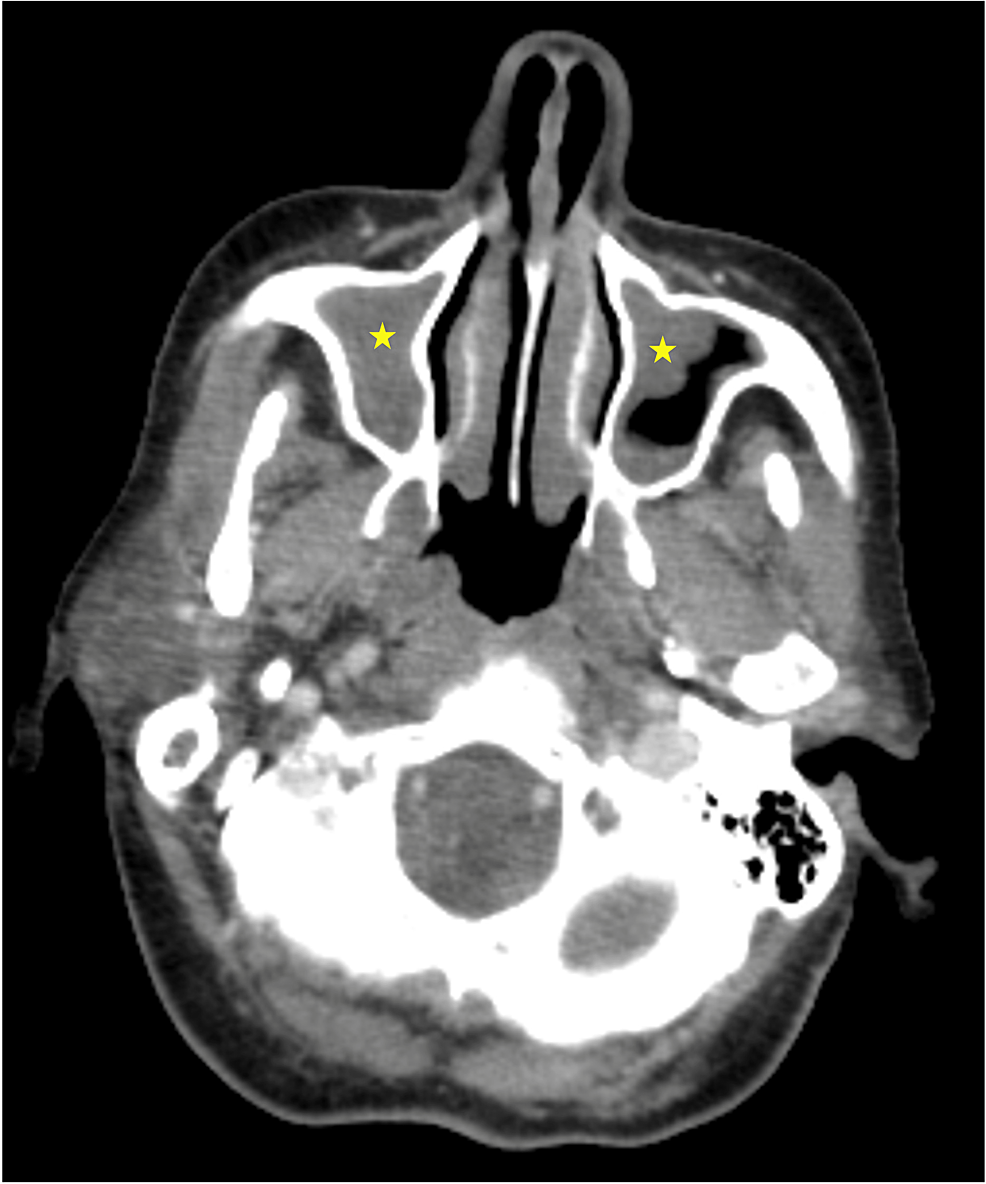

From www.bmj.com

Complications of rhinosinusitis The BMJ Red Flags For Sinusitis This article examines the symptoms, signs, presentation, investigation, and management of nasal and sinus neoplasia, and details the ‘red. Acute sinusitis (also commonly known as acute rhinosinusitis) is a symptomatic inflammation of the mucosal lining of the nasal cavity and paranasal sinuses, presenting. They are caused by mucosal inflammation, which inhibits mucociliary. Subtypes of rhinosinusitis include acute, subacute, recurrent acute,. Red Flags For Sinusitis.

From bjgp.org

Nose and sinus tumours red flags and referral British Journal of Red Flags For Sinusitis They are caused by mucosal inflammation, which inhibits mucociliary. Sinusitis (also known as rhinosinusitis) is a symptomatic inflammation of the mucosal lining of the paranasal sinuses and nasal cavity. Rhinosinusitis is one of the most common conditions for which patients seek medical care. Acute and chronic sinusitis are common primary care presentations. For those with signs of acute bacterial rhinosinusitis. Red Flags For Sinusitis.